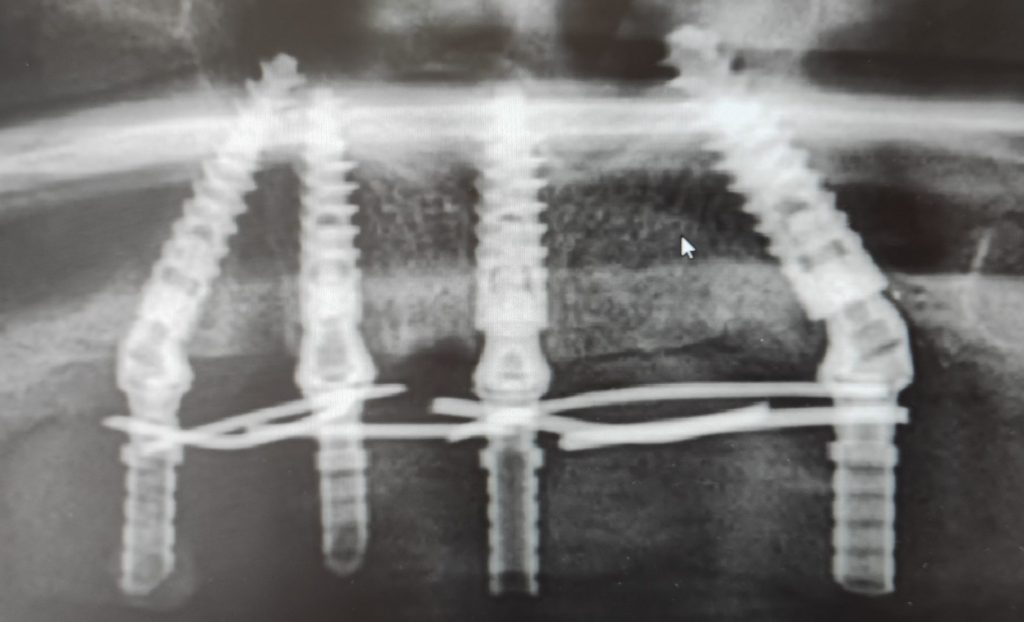

A foghúzást követően, még ugyanabban az ülésben került sor négy fogászati Alpha-Bio implantátum beültetésére a felső állcsontba. Az All-on-4 technológia lényege, hogy mindössze négy implantátummal stabil alapot teremtünk egy teljes fogívnyi pótláshoz. Két implantátum a front régióba, a másik kettő pedig hátul, döntött szögben került beültetésre, hogy kihasználjuk a meglévő csontot és elkerüljük az érzőidegeket. A beavatkozás helyi érzéstelenítésben zajlott.

A modern digitális tervezésnek köszönhetően a műtét gyors volt és pontos – egy teljes felső fogsor implantációja mindössze körülbelül egy órát vett igénybe. A négy titán műgyökér stabilan a helyére került, ezzel megteremtve az alapot a páciens új mosolyához.

Implantátumok felhelyezéséről röntgen